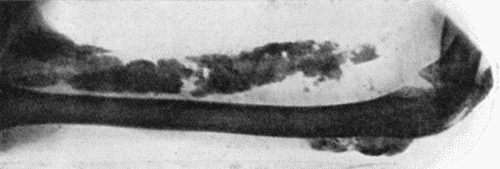

| 107. | Subungual Exostosis | 403 |